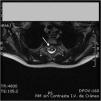

Lactante de 17 meses, con debilidad aguda de miembros inferiores (MMII) e irritabilidad, sin otra sintomatología acompañante ni antecedentes de traumatismo previo. Exploración: paraplejia flácida con nivel sensitivo D6, arreflexia en MMII, ausencia de reflejos cutáneos-abdominales y respuestas plantares indiferentes, siendo el resto de la exploración normal. Analítica básica incluyendo CK, normal. Ante la sospecha de enfermedad a nivel medular, como primera posibilidad una mielitis aguda, se realizó punción lumbar con LCR de características inflamatorias, iniciándose tratamiento con metilprednisolona intravenosa (30mg/kg/día). Horas más tarde presentó signos de disfunción autonómica (íleo paralítico, retención urinaria, priapismo). Ante la evolución rápidamente progresiva a síndrome medular completo grave, y para descartar completamente la posibilidad de comprensión extrínseca medular se realizó RM craneoespinal a las 36h del comienzo clínico, que mostró hematoma epidural espinal posterior desde D1 a L2, con edema medular desde C7 a D7 (figs. 1 y 2). Se practicó laminectomía y evacuación del hematoma, no encontrándose vasos patológicos intraoperatorios. La arteriografía espinal no mostró malformación vascular. La coagulopatía fue descartada. El paciente evolucionó hacia paraparesia espástica con vejiga neurógena.